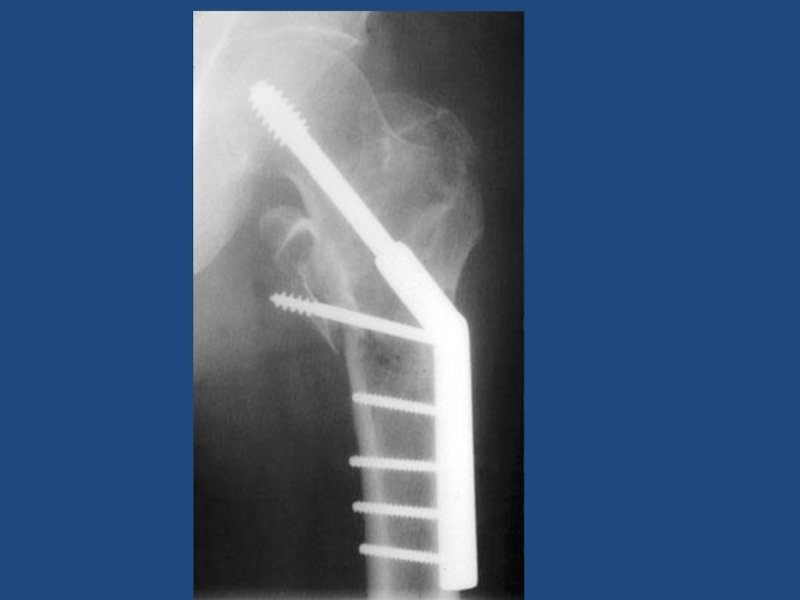

Вывих(выпадение) тазобедренного

эндопротеза слева и чрезвертельный перелом

17Вывих(выпадение) тазобедренного эндопротеза слева и чрезвертельный перелом